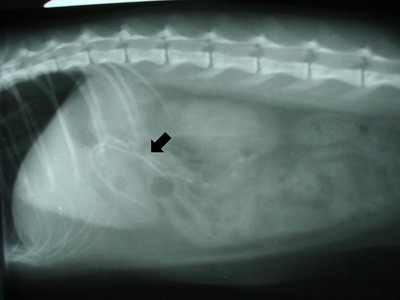

Na rentgenových snímcích bylo naštěstí lineární cizí těleso viditelné a nacházelo se na přechodu žaludku a dvanáctníku. Ve většině případů se umělá nebo gumová cizí tělesa na rentgenových snímcích rozeznat nedají.

RTG ukazující cizí těleso na přechodu žaludku a dvanáctníku RTG ukazující cizí těleso na přechodu žaludku a dvanáctníku